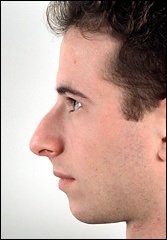

A fénykép a bal oldalon mutatja egy ember tipikus megnövekedett nazális gerinc. Ez jelentősen növeli az orrát előre. A fénykép után a művelet ugyanaz az ember nagyon jól néz ki.

Az operáció utáni képek labrum irányban függőlegesen felfelé.